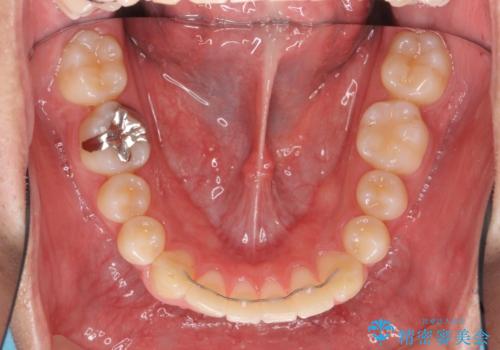

- ワイヤー矯正による治療後7年以上経過した患者様です。当時上の小臼歯を2本抜歯しています。

10代で矯正治療を行い、現在20代になられています。

矯正後8年目になりますが、並びも綺麗に保持でき、また上下の歯がさらにしっかり咬んできているのがわかります。

下は歯につけるタイプのワイヤーを貼っています。

さしたる問題もなく、半年~1年に一度のメインテナンスにお越しになっている患者様です。保定装置については、慣れれば習慣化するためさほど負担ではありません。

矯正をしなくても起こる下の前歯のがたつきも予防でき、若々しい歯並びを維持することができます。